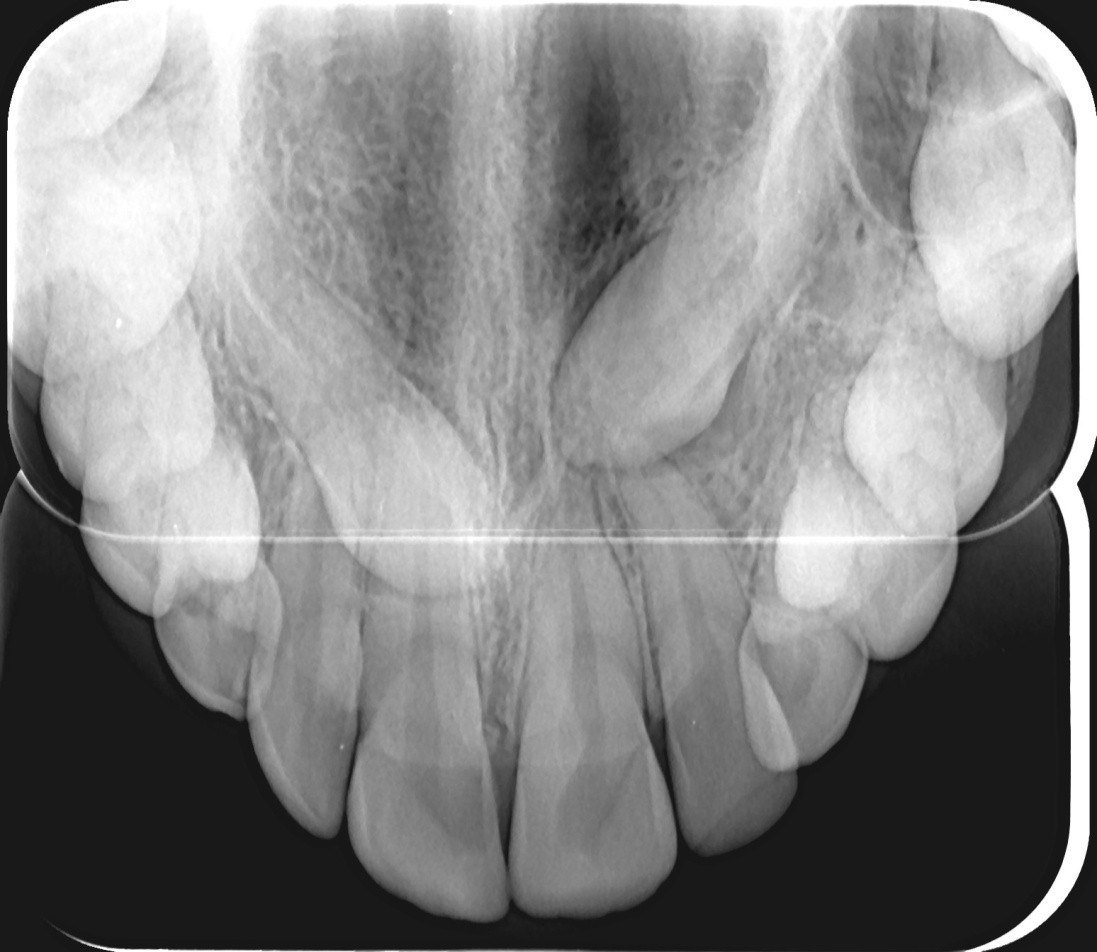

Descriere

Permite vizualizarea aranjării spațiale a formațiunilor de interes, de obicei incluse. În plus, radiografia ocluzală poate fi utilizată și la pacienții cu probleme ale glandelor salivare (ex: litiază de glandă submandibulară) sau la pacienții cu trismus (imposibilitatea deschiderii gurii datorită contracției musculare).